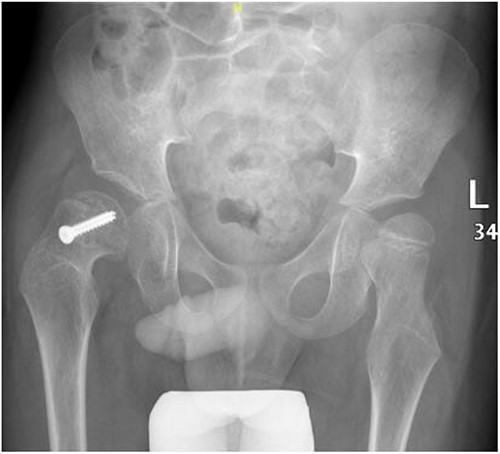

A 5-year-old independent ambulatory Middle Eastern boy with CP who was born preterm and developed grade III intraventricular haemorrhage and periventricular leucomalacia and was on AEDs, including valproic acid (VPA) and levetiracetam (LEV), for >3 years and was controlled over the last year (no history of seizure attack) presented to the emergency room (ER) with right hip pain and inability to bear weight for 4 weeks; the patient had no history of fever or trauma. Physical examination shows a thin, the weight is 12 kg, the height is 101 cm, vital signs within the normal range, tenderness over the right hip, and external rotation of the right hip, with restricted hip mobility. A radiological study was performed ~3 months before the patient presented to the ER for follow-up examination of a left hip coxa valgus deformity with no apparent abnormalities in the right hip (Fig. 1). Initial imaging studies conducted in the ER showed an anterior–posterior view of the pelvic radiograph, revealing Klein’s line [13] not intersecting the capital femoral epiphysis (Fig. 2), and frog-leg lateral view radiograph of the right hip (Fig. 3) confirmed SCFE and Southwick’s slip angle [13] of ~50° (moderate). Laboratory findings were clear for endocrine and renal diseases or infection, except for low vitamin D (total 25-OH Vitamin D: 43.4 nmol/L), suggesting vitamin D insufficiency. The diagnosis was confirmed with clinical and radiological studies as right-sided unstable SCFE requiring surgery. Surgical intervention was performed with percutaneous in situ fixation using a single fully threaded 4.5-mm cannulated screw (Fig. 4). Postsurgical rehabilitation included non-weight-bearing right lower extremities for 6 weeks. Regular follow-up with serial radiology studies showed stable fixation with no migration of screw or further slippage at 6 weeks (Fig. 5) and 3 (Fig. 6), 15 (Fig. 7), and 36 months (Fig. 8). During follow-up, a painless range of motion in the right hip was observed, with full weight-bearing and resumption of his usual activities with no complaints.

Pelvic anterior–posterior radiograph, 15 months following post-operative fixation.